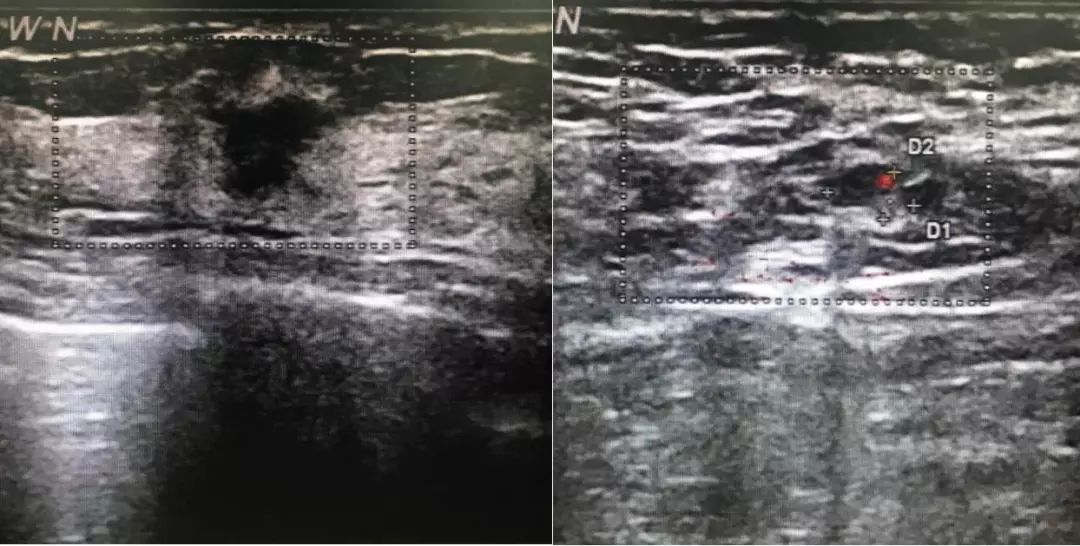

图1. 2018年8月15日行乳腺超声检查

2018年8月15日行乳腺超声检查:右乳外上11mm×9mm低回声区,边界不清晰,内部回声不均匀,未见明显血流信号。右腋下见淋巴结7mm×4mm,皮质稍增厚。超声诊断:双乳小叶增生,右乳低回声(BI-RADS 4B),右腋下淋巴结。2018年8月27日行双乳钼靶检查:双乳未见明显异常(BI-RADS 1)。